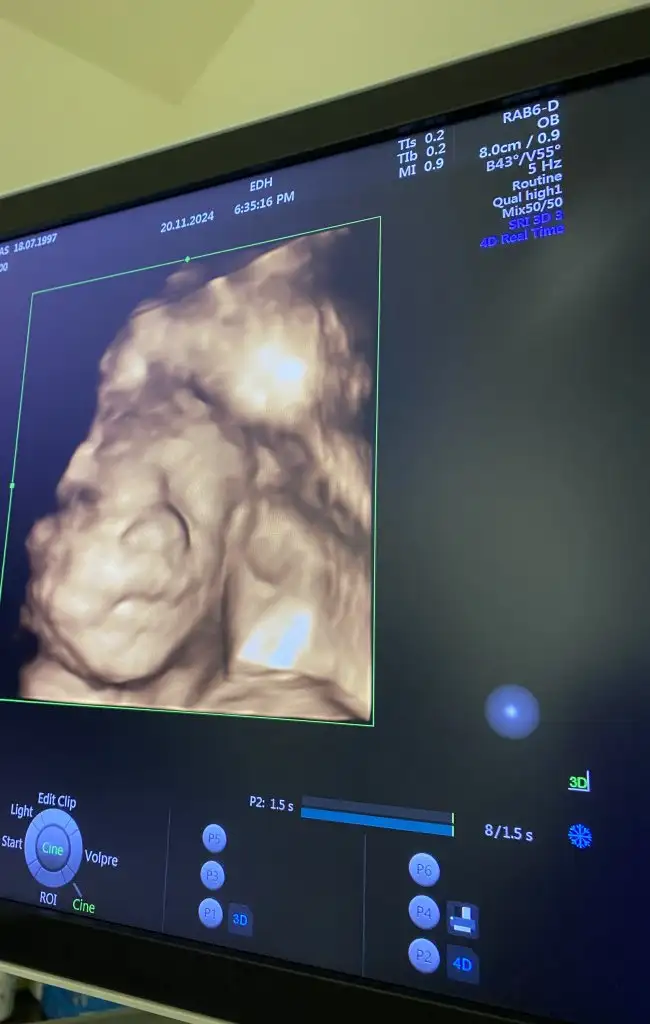

dur bir haftamız faln var sanırım bir de dahaYa bana dünyanın en güzel zorluğu gibi geliyor şuan ama üçüncü trimester a girdiğimi çok net anladım![]()

acaba bu her gittiğimizde ölçüyorlar tuhaf mi çıktı değerlerim hiç de aklıma gelmedi bakmak... Bu arada 25 haftaya giriyorum hafta ile ilgili olabilir mi ki